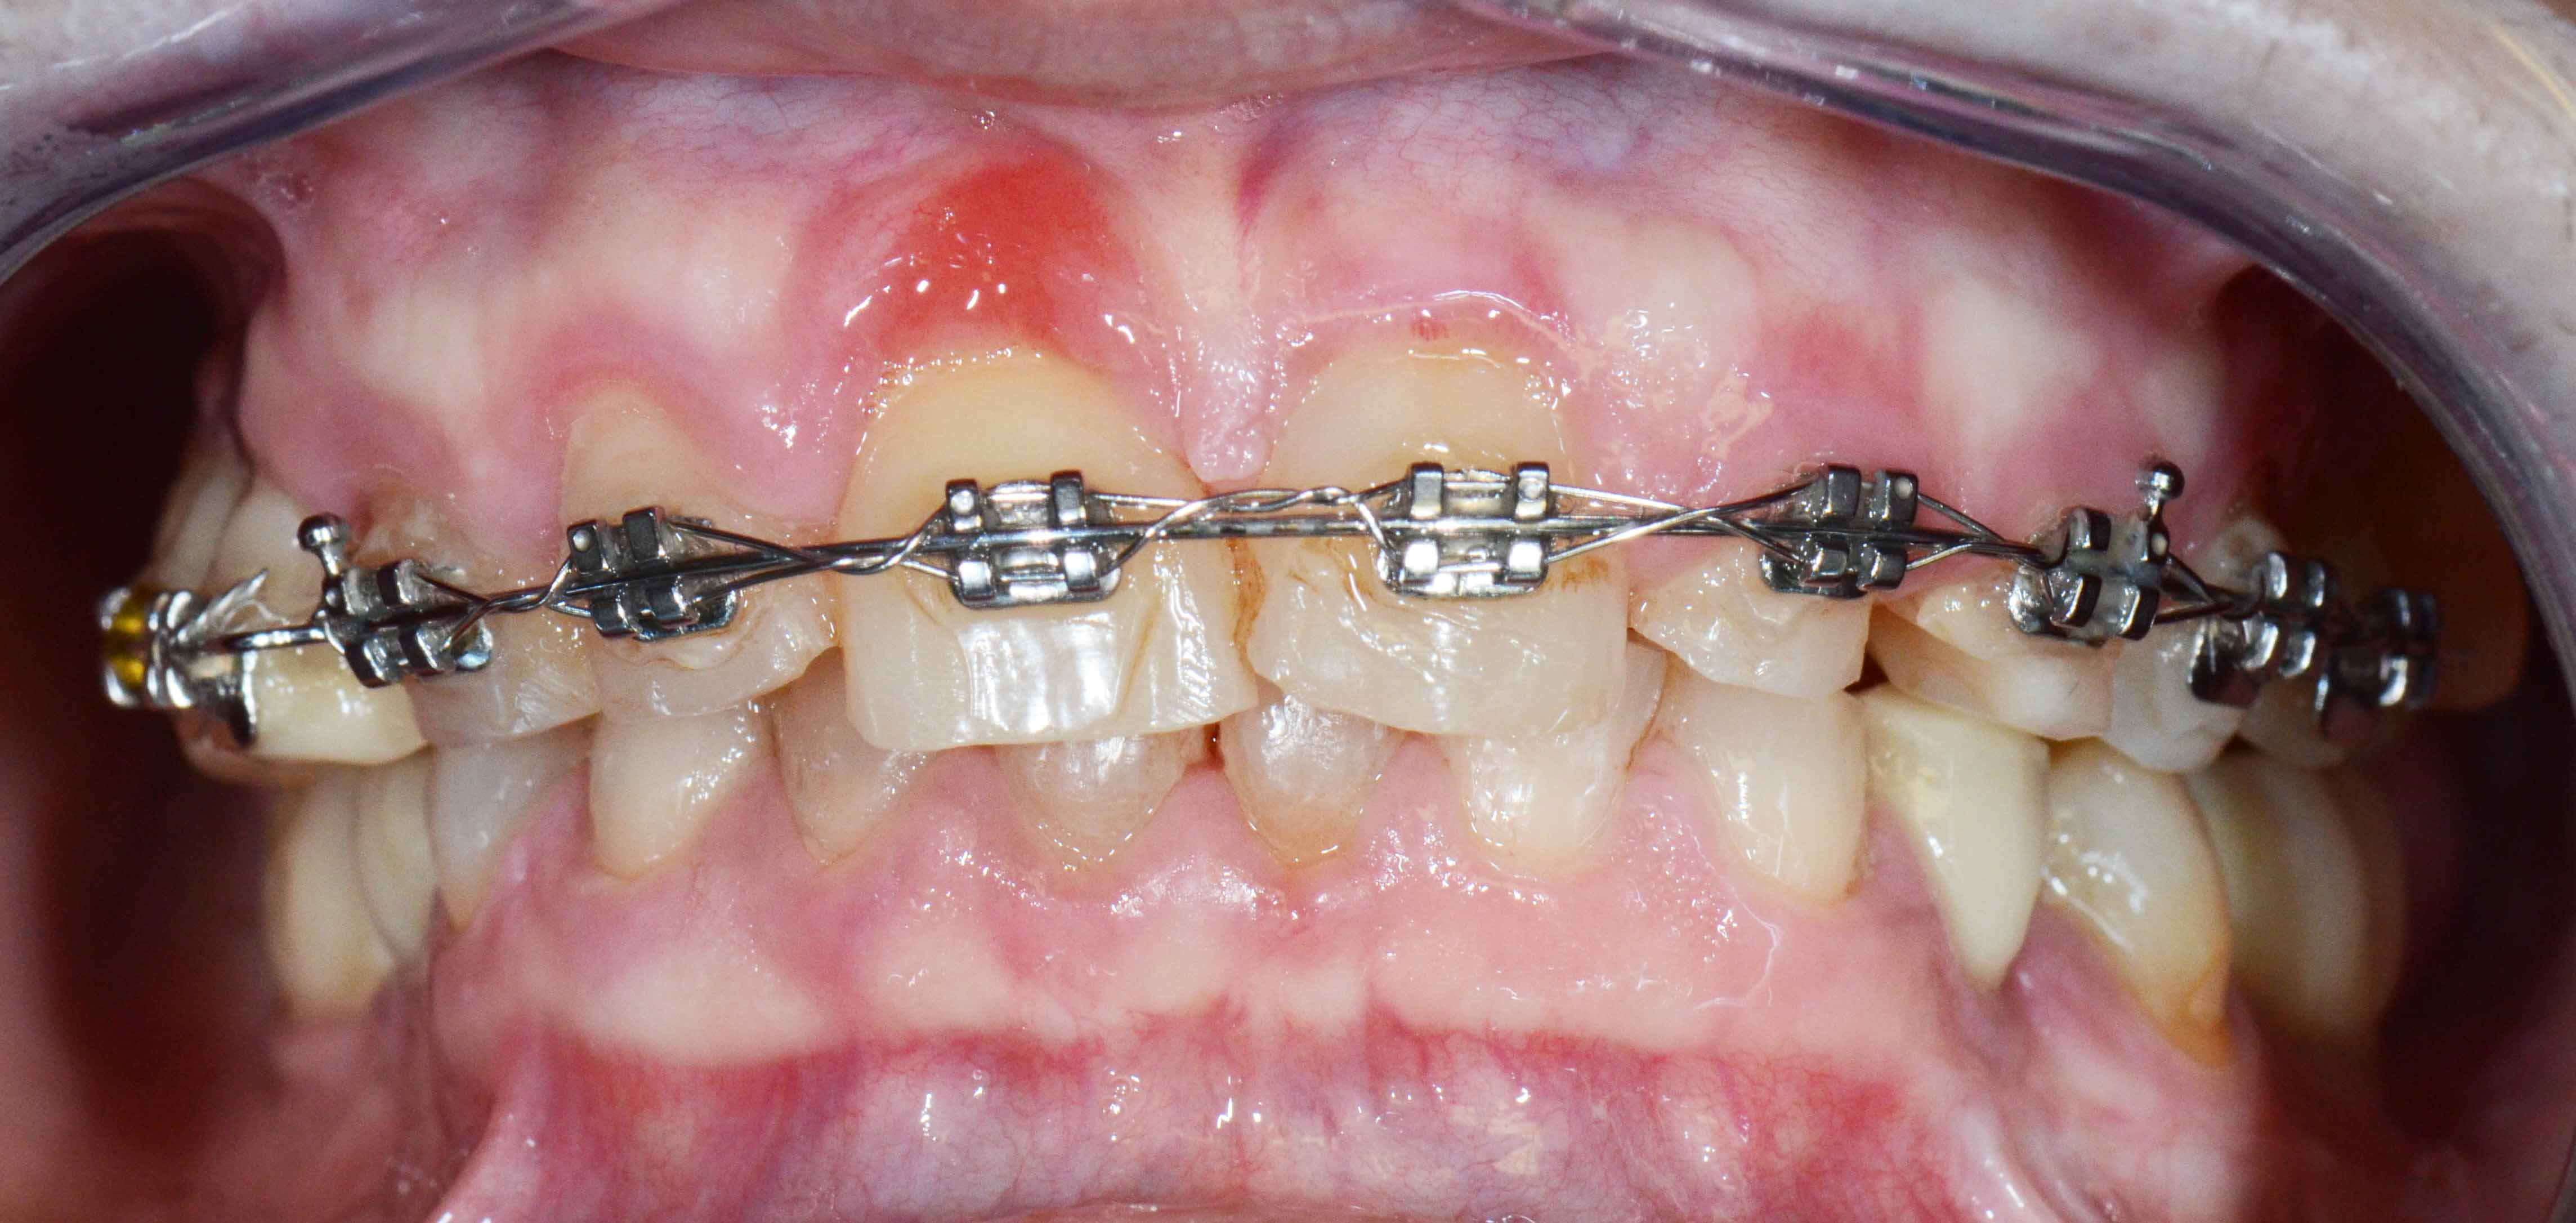

Complex Rehabilitation – The Treatment:

The natural teeth that had a good prognosis were kept and the ones that needed their position changed were moved by a fixed orthodontic brace.